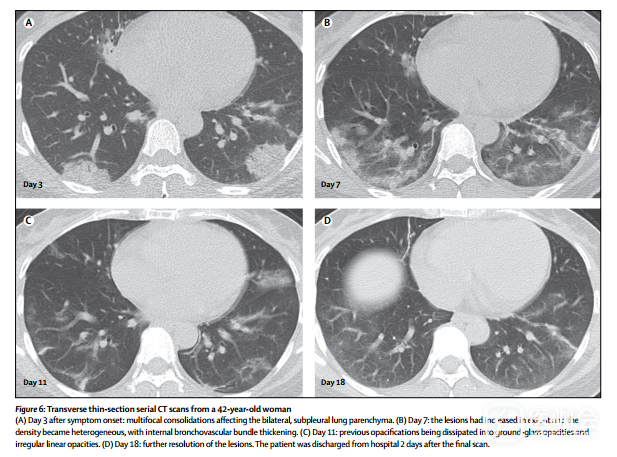

64例[79%]患者双侧肺受累,44例[54%]显示为周边分布,而36例[44%]显示为CT异常弥散分布(图2)。胸部CT最常见毛玻璃样征(GGO)(53 [65%]例患者;图2A),还有边缘不明确(66 [81%]),小叶间隔平滑或不规则增厚(28 [35%]; 图2A),空气支气管征(38 [47%];图2A,D),碎石路征(crazypaving pattern)(8 [10%];图2B)和相邻胸膜增厚(26 [32%])。 较少见的CT表现为结节(5例[6%]),囊性变化(8例[10%];图2C),支气管扩张(9例[11%]),胸腔积液(4例[5%];图2D),和淋巴结肿大(5 [6%])。本研究病例中未观察到肿块,空化和钙化。

图2 入组患者的横向薄层CT扫描影像